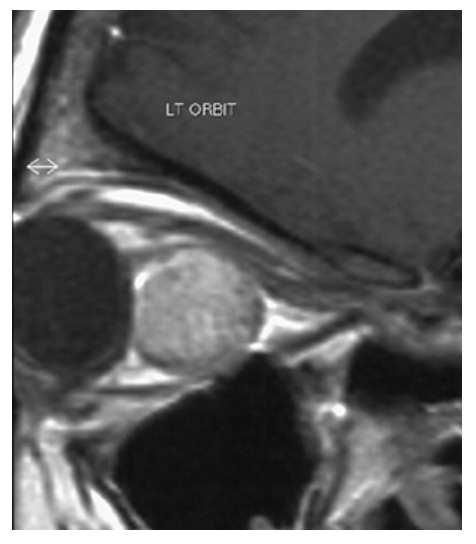

What does the figure show?

Cavernous Hemangioma. Sagittal T1-weighted postcontrast MR shows round, slightly hyperintense, retrobular mass displacing optic nerve superiorly.